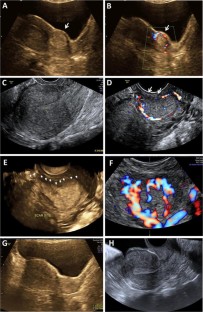

Pitfalls in Ultrasound Diagnosis of Cesarean Scar Pregnancy

Cesarean scar pregnancy (CSP) is a rare kind of ectopic pregnancy implanted in the previous cesarean scar and has an increasing incidence over the past 30 years. As the suspicion is low, the diagnosis may be delayed or misinterpreted in ultrasound, leading to treatment strategies that might end up in uterine rupture or hysterectomy. The objective here is to review the ultrasound findings in CSP with varied presentations. Transabdominal and transvaginal sonography combined with color Doppler is a reliable tool for the diagnosis of CSP. When the gestational sac is seen in lower part of the uterine cavity, differentiation between threatened miscarriage, cervical pregnancy and CSP could be difficult. Not all cases of CSP present with typical ultrasound findings and a high index of suspicion is needed for diagnosis in these cases. An attempted curettage or MTP pill taken in an undiagnosed CSP often alters the typical findings. The possibility of CSP should also be considered in cases presenting with abnormal uterine bleeding and have a prior history of cesarean section. With lack of awareness about this condition, the diagnosis can often be missed either with MRI or in ultrasound. Correct interpretation and timely diagnosis save the mother from life-threatening complications and also preserves future fertility.

Fig. 1

Fig. 2

Fig. 3

Fig. 4

Fig. 5